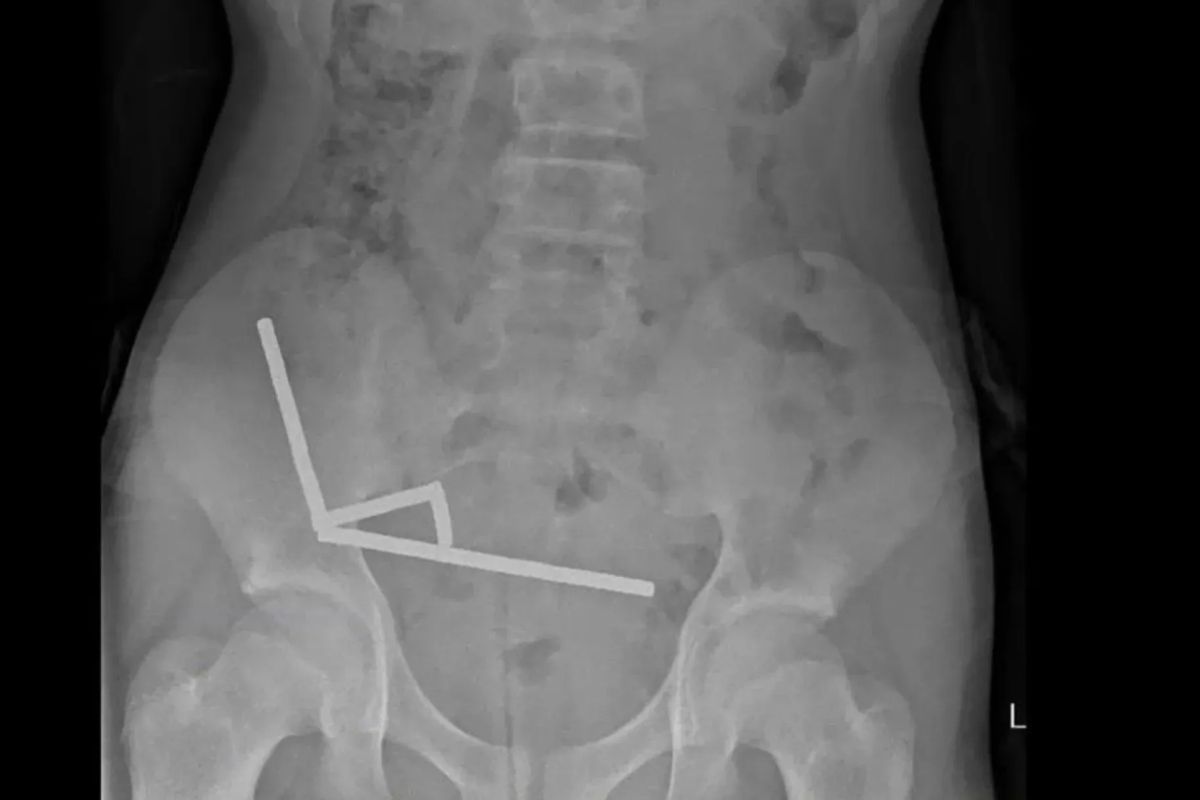

Mivel a világ legerősebb mágnestípusa, a neodímium 2013 óta be van tiltva Új-Zélandon, a 13 éves fiú a Temuról rendelte meg száz darabot. Meg is érkeztek az 5x2 milliméteres kis mágnesek, amelyeket a fiú valamiért lenyelt. Ez nem volt jó ötlet, ugyanis a mágnesek – meglepetés! – egymáshoz tapadtak odabenn, négy egyenes vonalban felsorakozva a gyermek belében.

Négy nap hasi görcs után a fiút a North Island-i Tauranga Kórházba szállították, ahol megműtötték. Az orvosok szerint a mágnesek nyomása négy területen a szövetek elhalását, vagyis nekrózist okozott a vékonybélben és a vakbélben. A sebészek eltávolították az elhalt szöveteket és kivették a mágneseket, majd a gyermek nyolcnapos kórházi kezelés után hazatérhetett.